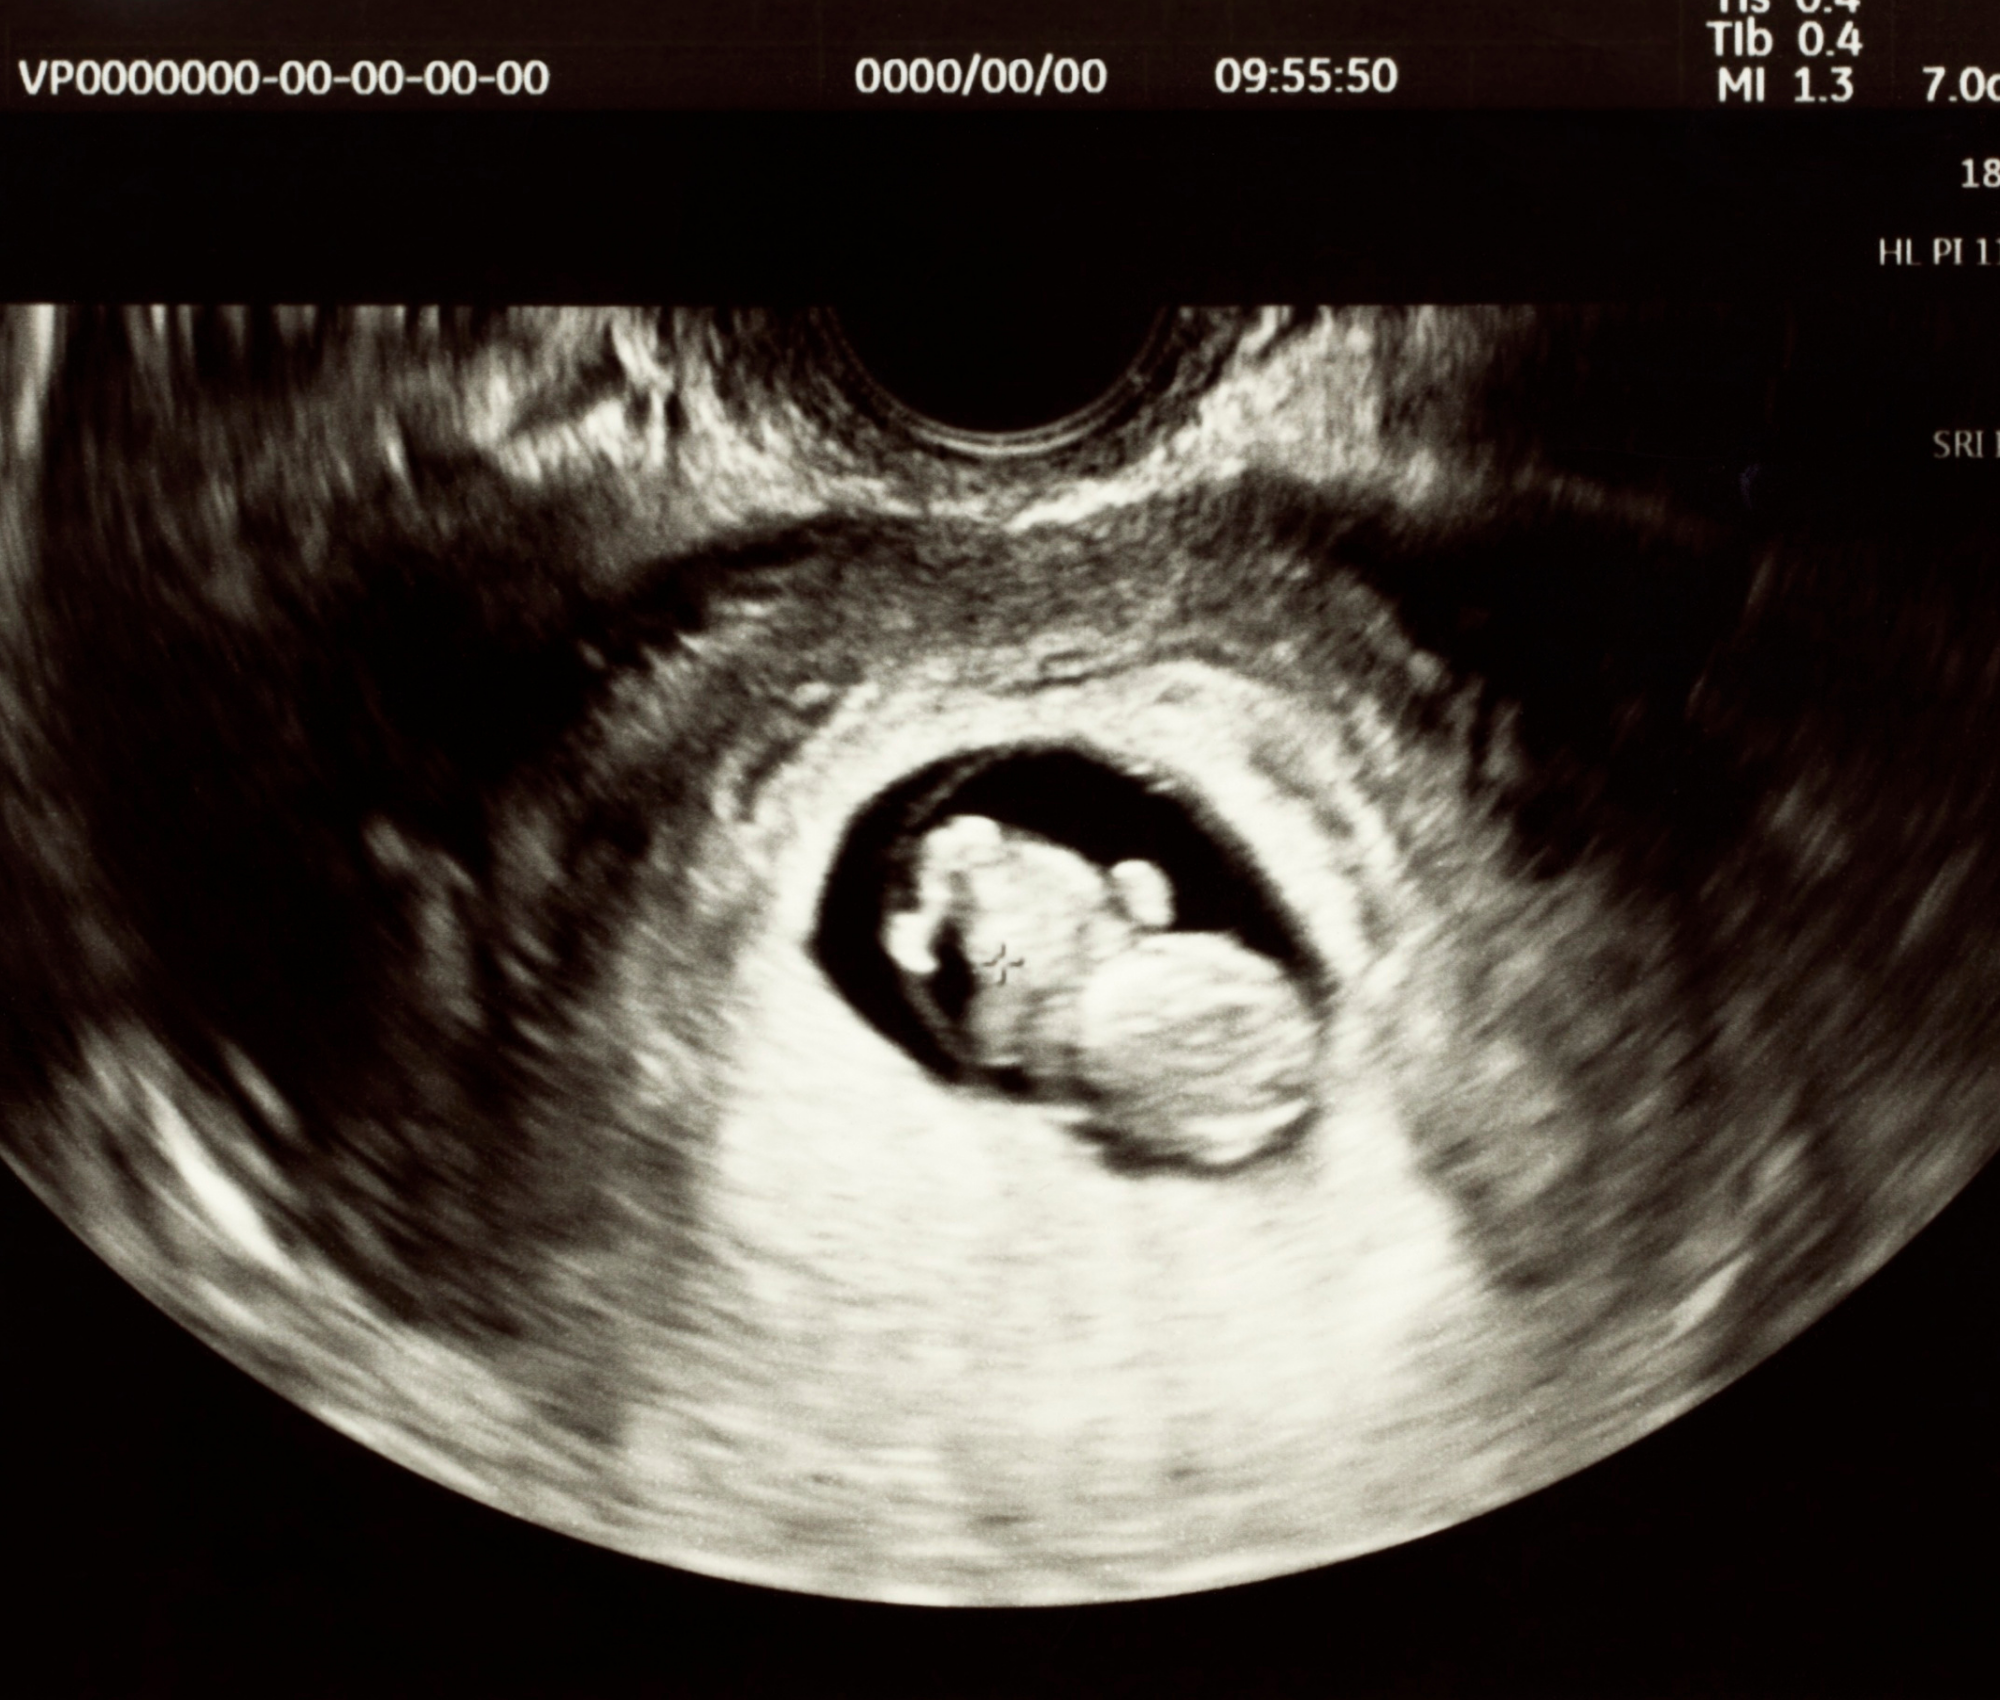

Lighthouse nurses and sonographers have performed over 12,500 ultrasounds — all read by a volunteer radiologist.

The Hawthorne center includes a full medical suite staffed by eight nurses and sonographers across all four locations. Their flagship service is a free limited obstetric ultrasound — performed by a trained nurse or registered diagnostic medical sonographer (RDMS) and read by a volunteer radiologist who has reviewed all 12,500+ scans completed to date.

Jan, who oversees the medical team, walked the group through the ultrasound room during the tour, pointing to silicone life-sized fetuses organized by gestational week — 9, 10, 11, 12, 14 weeks — each one showing a recognizable developing baby.

The ultrasound serves several critical functions beyond the emotional:

Confirms pregnancy and establishes gestational age — many women arrive thinking they're 6 weeks along and discover they're 12

Screens for ectopic pregnancy, a life-threatening condition whose symptoms overlap with those of the abortion pill

Provides documentation that clients can use to apply for New Jersey Medicaid and prenatal care referrals

Lighthouse does not refer for abortion, but both Debbie and Jan were clear throughout the tour: the approach is entirely permission-based. Clients choose whether to view the ultrasound screen. Some ask not to see it. Some change their minds at the end and ask for a picture. The goal is informed decision-making, not pressure.